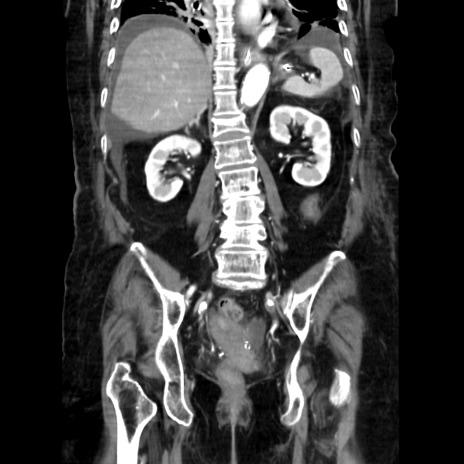

症例40(冠状断像)

【症例】90歳代女性

【主訴】腹痛・嘔吐

【現病歴】 食欲低下、嘔吐があり昨日他院受診。肺炎と診断され入院となる。入院後より腹部全体に圧痛あり。胃管留置され経過みていたが、症状持続するため、

当院転院となる。

【既往歴】胸椎圧迫骨折、胆石症

【身体所見】腹部:中央に激痛あり、圧痛あり、反跳痛不明

【データ】WBC 17100、CRP 18.82

冠状断像